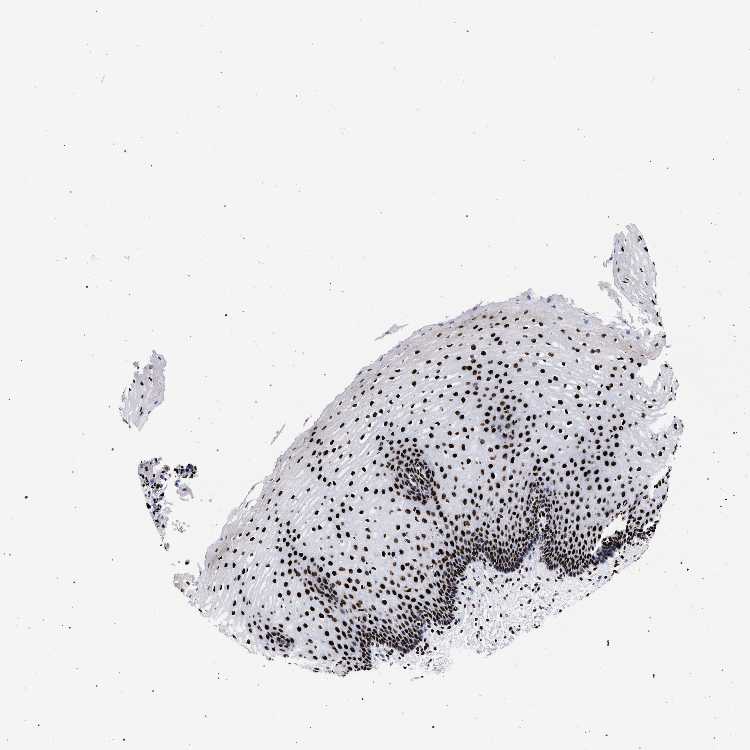

ESOPHAGUS - Antibody stainingi

Antibody staining in the annotated cell types in the current human tissue is reported as not detected, low, medium, or high, based on conventional immunohistochemistry profiling in selected tissues. This score is based on the combination of the staining intensity and fraction of stained cells.

Each image is clickable and will lead to virtual microscopy that enables deeper exploration of all samples and also displays staining intensity scores, fraction scores and subcellular localization as well as patient and tissue information for each sample.

Antibody HPA001609Antibody HPA001666Antibody CAB010894

Squamous epithelial cells HighHighHigh